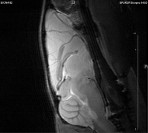

Small Animal Multimodal Imaging

Magnetic Resonance